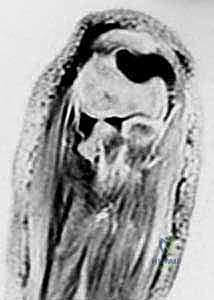

3. التصوير المقطعي المحوسب (CT Scan)

في حالات الكسور المتفتتة المعقدة (مثل ميسون النوع الثالث)، أو عند التخطيط لعملية جراحية دقيقة تتطلب إعادة بناء المفصل، يطلب الدكتور هطيف إجراء تصوير مقطعي ثلاثي الأبعاد. يوفر هذا التصوير خريطة دقيقة لحجم وموقع كل قطعة عظمية، مما يسهل اختيار نوع الشرائح والمسامير المناسبة.